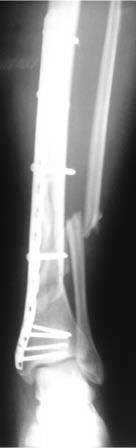

первичные снимки b послеоперационные качеством получше.

Уважаемый Максим!

Было у меня нечто подобное, поверте старому доктору, только реостеосинтез и с максимальным радикализмом. Я бы в данной ситуации сделал следующее. Учитывая практически одноуровневость перлома, обязательно синтезировал малоберцовую кость, а после этого установил бы блокированный стержень в большеберцовую (естественно убрав предварительно раннее установленную конструкцию). Повторное использование металла ни к чему хорошему не приведёт.

И ещё в плане совета, пластина с угловой стабильностью может использоваться как с винтами простыми так и с винтами с угловой стабильностью, но при одном остеосинтезе обе методики совмещать не надо.

Перелом внесуставный, зачем вообще было пластиной делать. У нас бы - минимально инвазивное удаление пластины, дистрактор (плюс малоберцовую временной спицей к tibia или тарану), и гвоздь с 3-4 винтами в дистальный отломок. Малоберцовую трогать не видно необходимости, восстановления длины обеих костей при неповрежденном голеностопном суставе вполне достаточно.

Максим, привет! Здесь мы имеем дело с внесуставным переломом пилона (тип А). Синтезировать или нет малоберцовую- вопрос скорее уже риторический, но вот выбрать ее длину надо было изначально (дистрактором ли или синтезировать накостно). Мне кажется именно в этом ошибка. Не повторяй ее повторно- используй дистрактор,ее длина пусть будет ориентиром для коррекции остаточной деформации большеберцовой, а далее что есть- пластина, гвоздь...